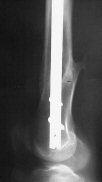

Attached are few examples from our Hospital:

B. Fixation loosening: distal cutting of the nail, non-unions do happen (cases attached).

Locking Plating has more distal screws than any nail, fixed angles and provides much better fixation, especially in osteoporotic bone.

Dr. Melamed: Principles for LISS and LCP are the same, again - LISS has outrigger helping for more percutaneous technique.